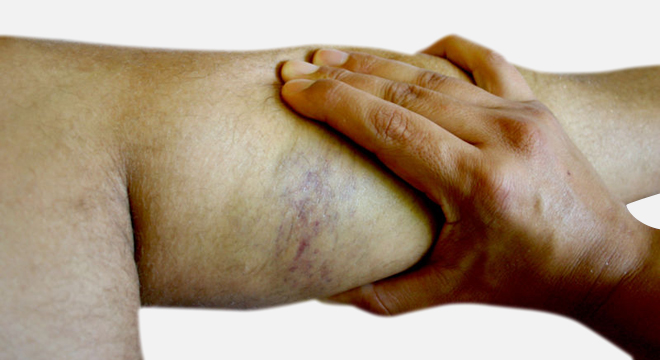

Muskelzerrung: starke krampfartige Schmerzen, Dellen, Bluterguss

Beschwerden, die auf eine Muskelzerrung hindeuten können, sind unter anderem:

• Druck-, Dehn- und Anspannungsschmerzen

• Bei Muskelzerrung eher zunehmender, krampfartiger Schmerz, bei Muskelfaserriss eher akuter, stechender Schmerz

• Bei grösseren Muskelfaserrissen (Ab Grad II) werden Dellen im Muskel sichtbar, beim vollständigen Riss, evtl. eine starke Vorwölbung

• Die Funktion des Muskels bzw. des betroffenen Gliedes ist ab Grad II Muskelfaserrissen eingeschränkt

• Im Laufe der Zeit Schwellung durch Blutungen bei gröberen Verletzungen